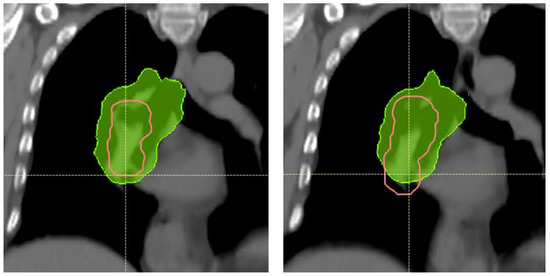

3.3. Target Dose Robustness at Plan and Start

3.5. Target Coverage and OAR Sparing at Start